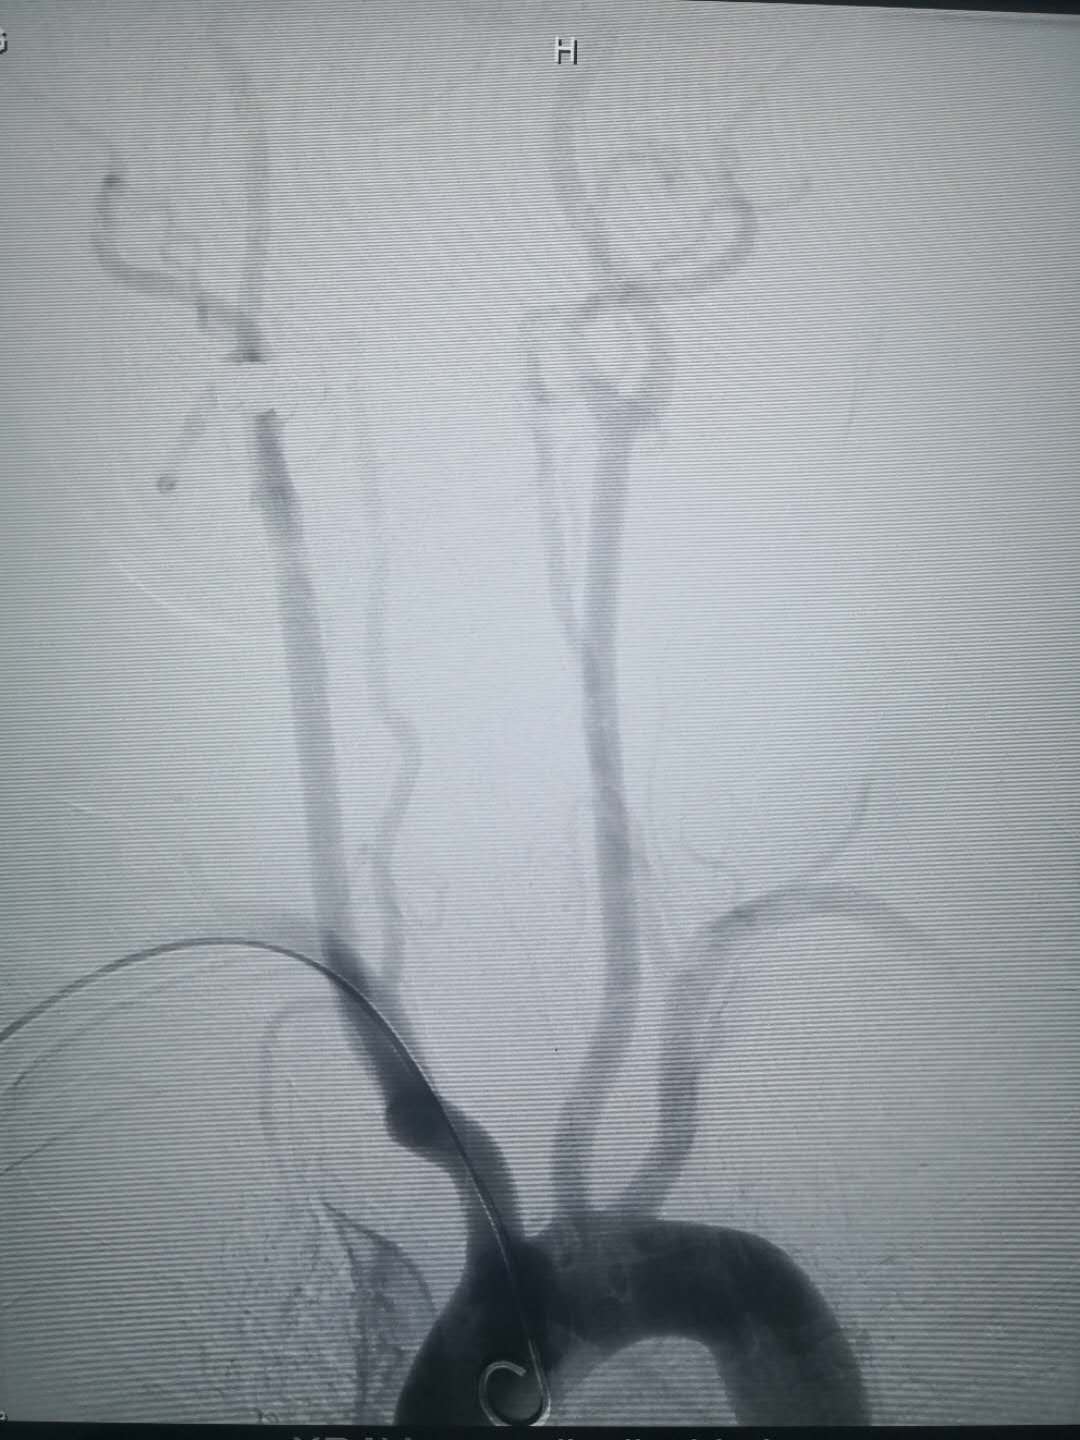

置入造影导管后相关血管造影图,所选择的血管清晰可见

经动脉鞘管置入造影导管行造影术 经桡动脉穿刺置入动脉鞘管 术后:使用小巧的桡动脉压迫器压迫固定桡动脉